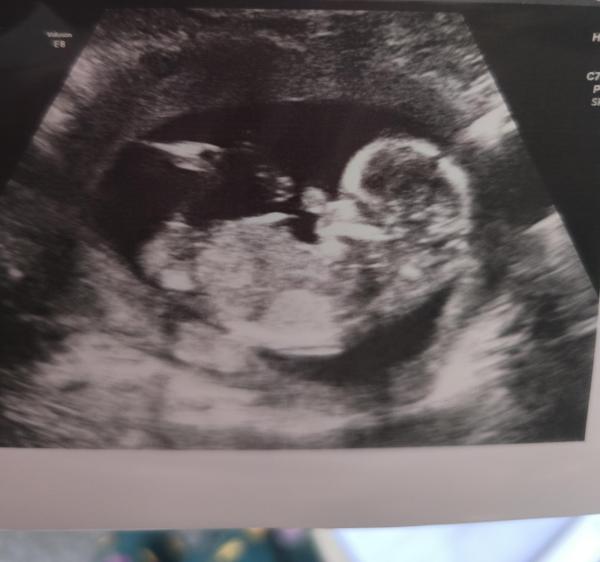

Hallo ihr Lieben, ich bin total unsicher ist das der Nub zu sehen oder ist das nur Wunschdenken? Liebe Grüße

Bild zu Nub erkennbar oder nicht? - Schwanger - wer noch? Rund um die Schwangerschaft

Ja Nub ist kurz und hoch, spricht für einen Jungen :)